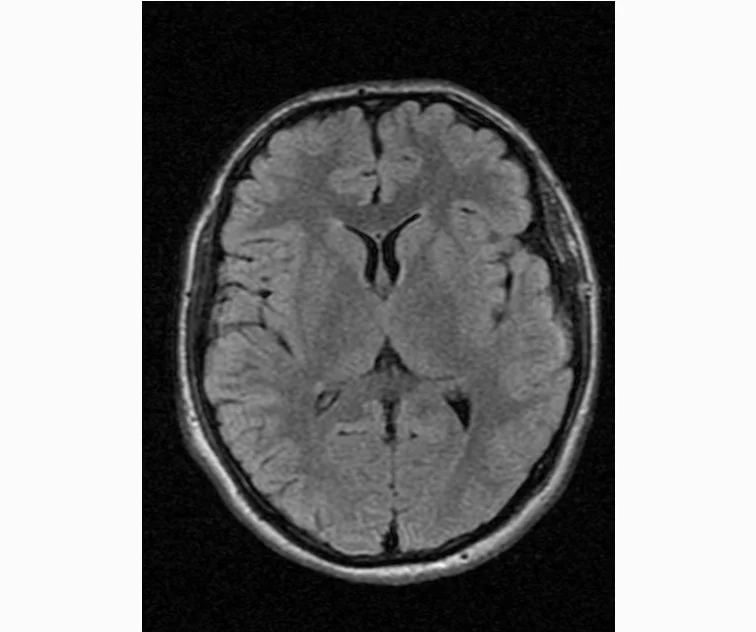

делал в обласной на siemense.В заключении выданом мне через 15мин.после мрт (легкая дегидрация)

Меня смутил факт выдачи заключения через 10мин(наверно они у них зарание напечатаные)я не медик.достаточно мимолётного взгляда на снимки?А вы видете на них гидроцефалию? Я лиш спросил куда идти с результатами томографии?и не хотел никого роздражать.

Я попросил взглянуть на снимки и сказать видна.ли на них гидроцефалия?или куда обратится за консультацией по этому вопросу?В мрт снимках наверно розбирается любой нервопатолог(я так предположил)

Я уже говорил, что независимо от того, есть на МРТ гидроцефалия или нет, лечиться тебе нужно только в том случае, если есть какие-либо проявления болезни, иначе на все эти анализы можешь забить... Но давай все-таки разберемся с томограммой.

Итак, с самого начала томограмма обозначала срез какого-либо органа на определенной глубине, позволяла заглянуть вовнутрь. При компьютерной томографии аппарат делает десятки срезов головного мозга в разных направлениях и из этого множества срезов он моделирует полноценное объемное изображение мозга в натуральную величину. Обрати внимание, компьютер работает не с этими миниатюрными изображениями, а с трехмерной моделью в масштабе 1:1. Эту модель вдоль и поперек анализирует суперсовременный компьютер, выполняющий миллионы операций в секунду. Только ***** может пытаться перепроверить компьютер, ведь человеку не хватит всей жизни чтобы проанализировать то, что компьютер с тобой сделал за 10 минут. Я хочу, чтобы ты это понял!

Ты разместл здесь несколько миниатюр и хочешь, чтобы врач по ним создал полноценное объемное изображение в натуральную величину, а потом осмотрел его со всех сторон и дал заключение? Но ведь это невозможно. Это просто насмешка над врачом, это издевательство над здравым смыслом. Принеси Букеру уменьшенный в 50 раз снимок зуба и спроси у него, в каком состоянии там корневые каналы. Или давай я дам тебе скрин со спутниковой карты города и попрошу тебя описать, какого цвета и какой модели запечатленная со спутника машина, какой у нее гос.номер, сколько в ней пассажиров, сколько из них мужчин и сколько женщин...